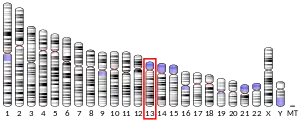

| External IDs | OMIM: 607111 HomoloGene: 32243 GeneCards: SPART | ||||||||||||||||||||||||||||||||||||||||||||||||||